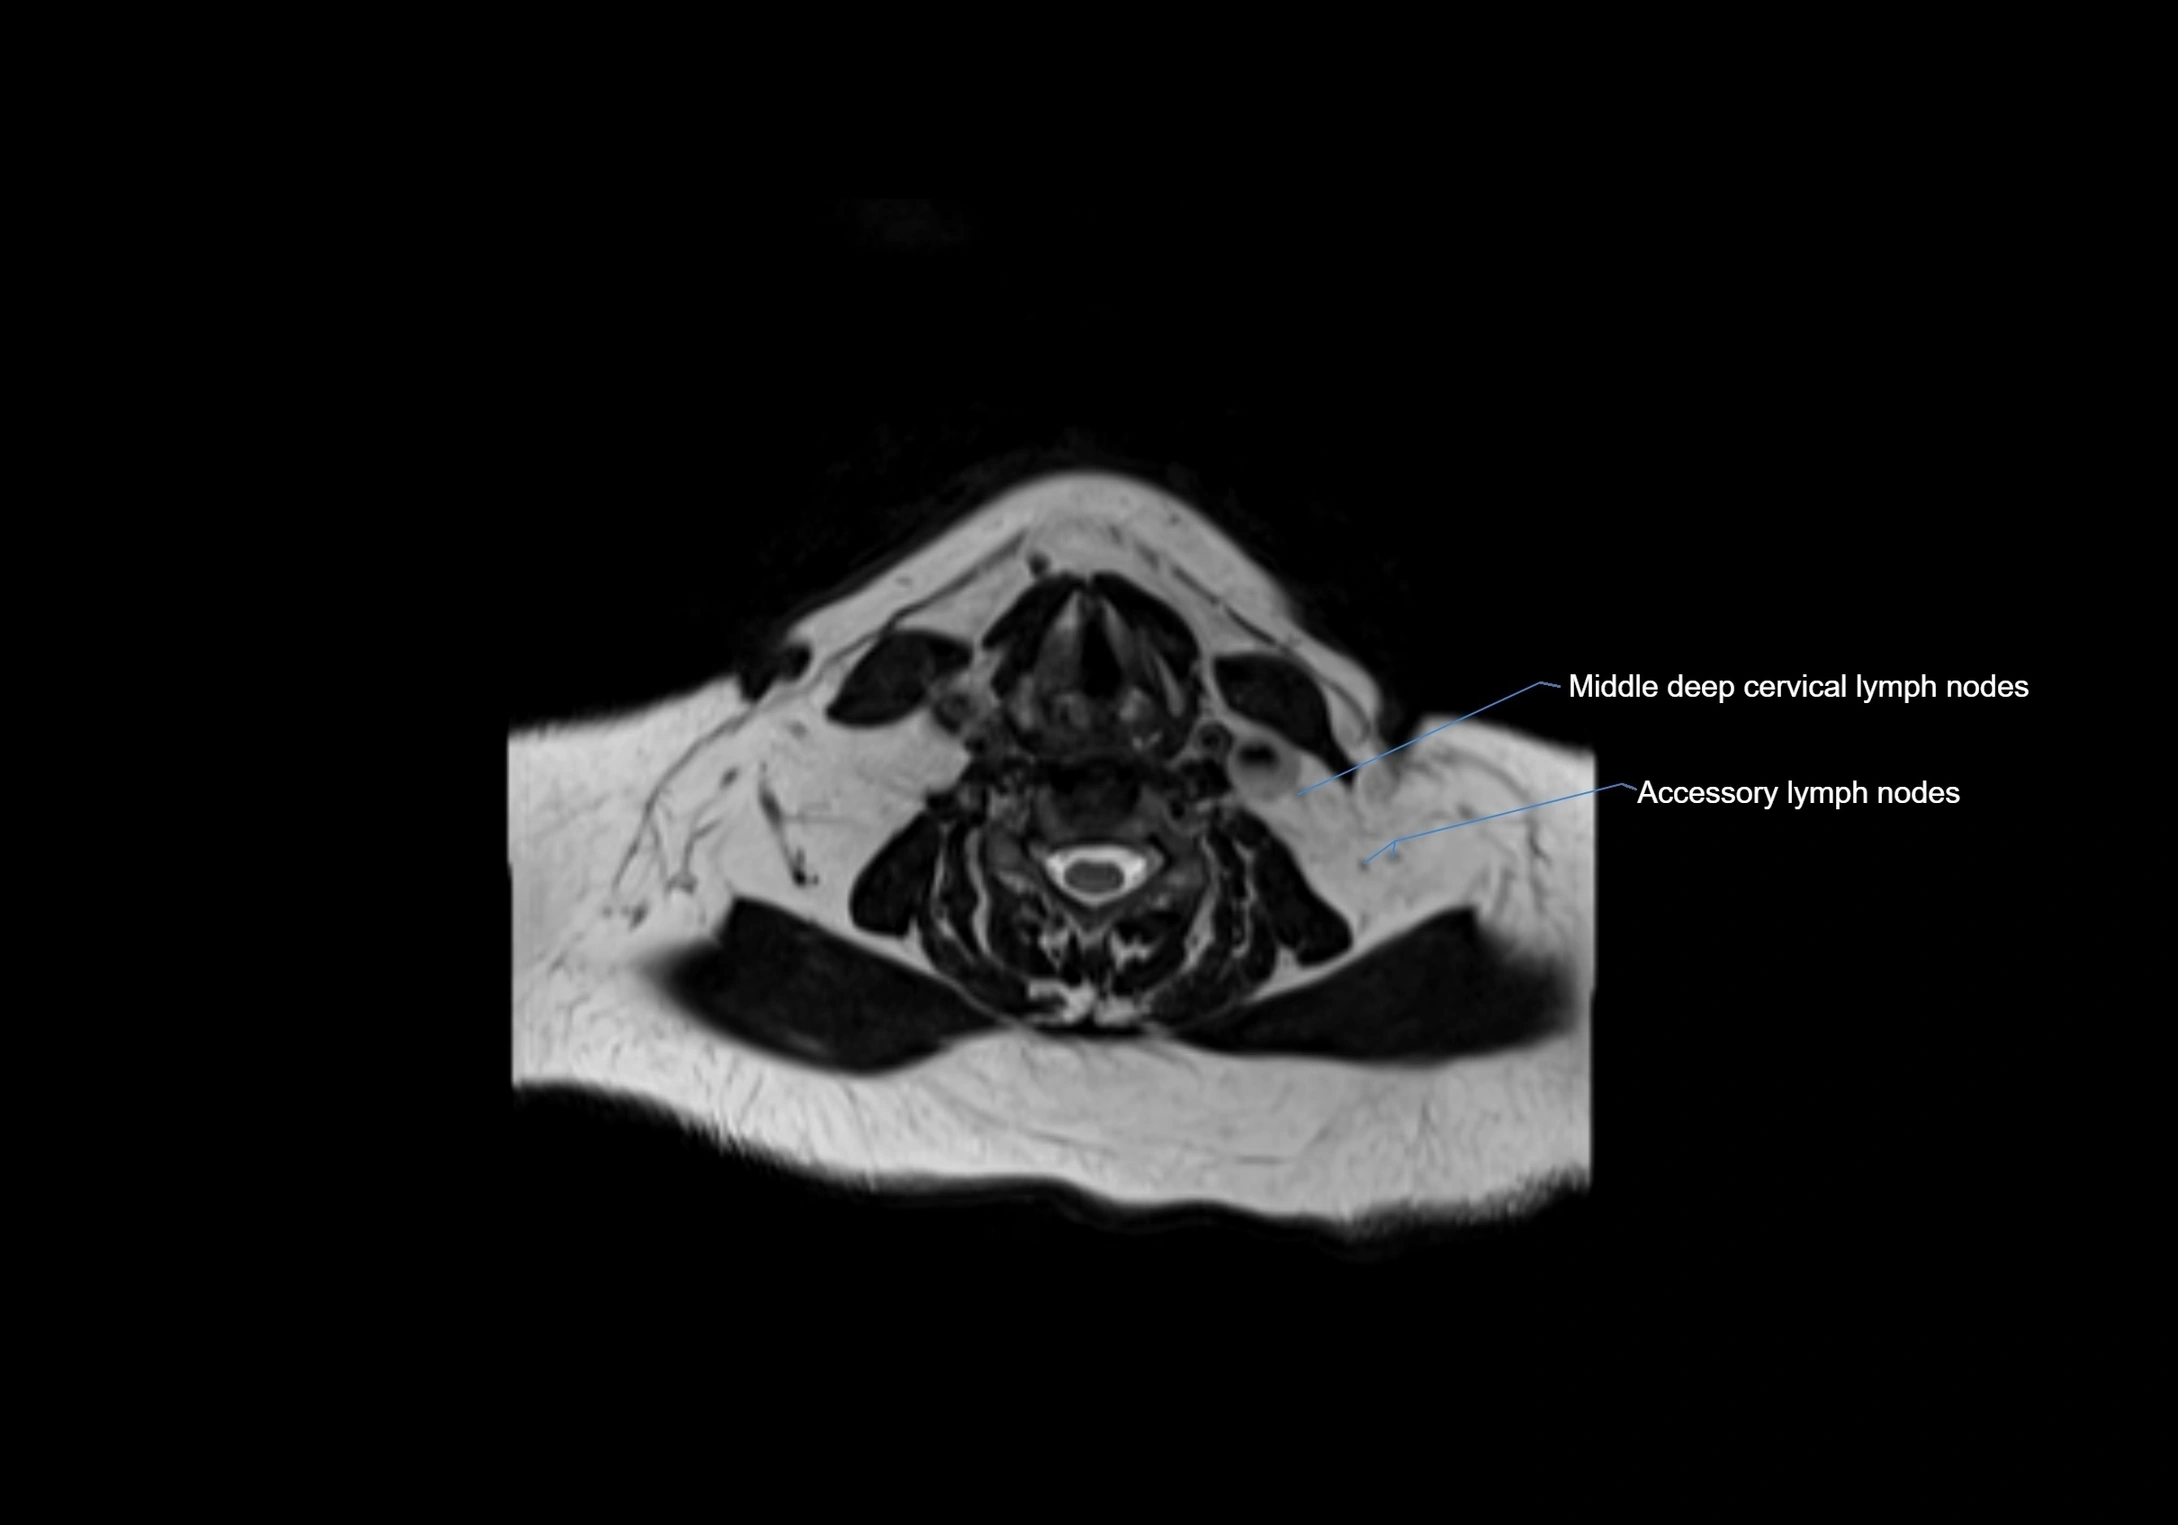

Location

• Found along primary lymph node chains, including preauricular, submandibular, parotid, and occipital regions

• Embedded in subcutaneous fat or superficial fascia, often lateral or posterior to primary nodes

• Variable in number; may occur unilaterally or bilaterally, depending on individual anatomy

MRI Appearance

T1-weighted images:

• Normal accessory nodes appear as small, oval hypointense to intermediate signal structures within subcutaneous fat

• Surrounded by hyperintense fat, enhancing contrast for visualization

• Pathological nodes may appear enlarged or rounded, sometimes with cortical thickening

CT Appearance:

• Nodes appear as small, soft tissue density structures embedded in subcutaneous fat near primary lymph nodes

• Surrounded by air in adjacent facial cavities or normal soft tissue, providing natural contrast

• Enlarged or pathological nodes appear as well-defined or irregular soft tissue masses

• CT is particularly useful for preoperative assessment, infection evaluation, or detection of metastatic spread

MRI images